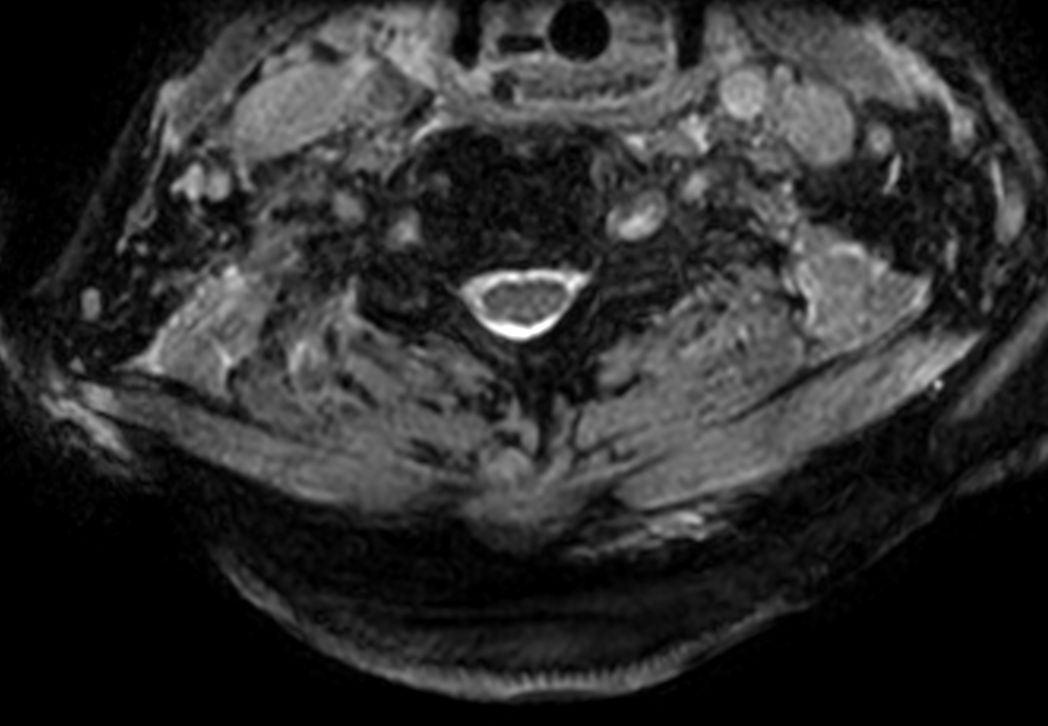

Cervical Spine - Cord lesion

mFFE SPIR